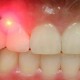

ایمپلنت (کاشت دندان) چیست ؟

ایمپلنت دندانی به پیچ ساخته شده از جنس تیتانیوم گفته میشود که در استخوان فک کاشته میشود و جایگزین دندان از دست رفته میشود پس از جایگذاری ایمپلنت طی روندی که یکپارچگی استخوانی نام دارد ایمپلنت محکم به استخوان جوش می خورد سپس روکش یا دست دندان بر روی ایمپلنت متصل میشود.